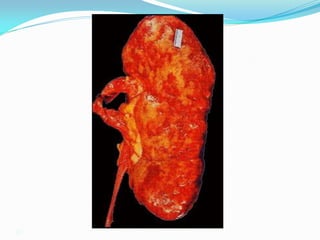

Vỏ tủy không phân biệt rõ.Thận

teo < 80mm (trừ ĐTĐ, thận đa

nang, thoái hóa tinh bột…)